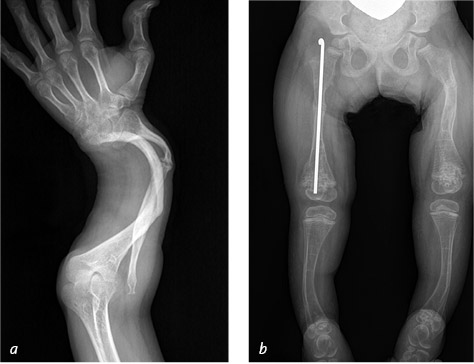

Иллюстрация к книге — Кости: внутри и снаружи [i_022.jpg]

Несовершенный остеогенез стал причиной множественных переломов предплечья, которые зажили с явными деформациями (a). Металлический штифт, вставленный в центральный канал кости, снижает риск перелома и помогает сохранить правильное расположение отломков, если перелом все же произойдет (b)

Benjamin Plotkin, MD (a); Richard E. Bowen, MD (b)